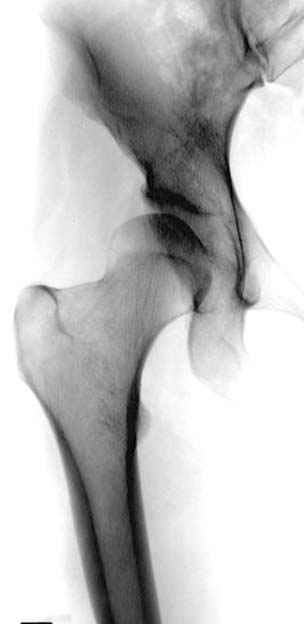

Рис.2 Та же трехмерная модель тазобедренного сустава без аналога связки головки бедра. Пружина динамометра удерживает тазовую часть модели от опрокидывания, поддерживая стабильность так же, как отводящие мышцы обеспечивают ее в отсутствии связки головки бедра.